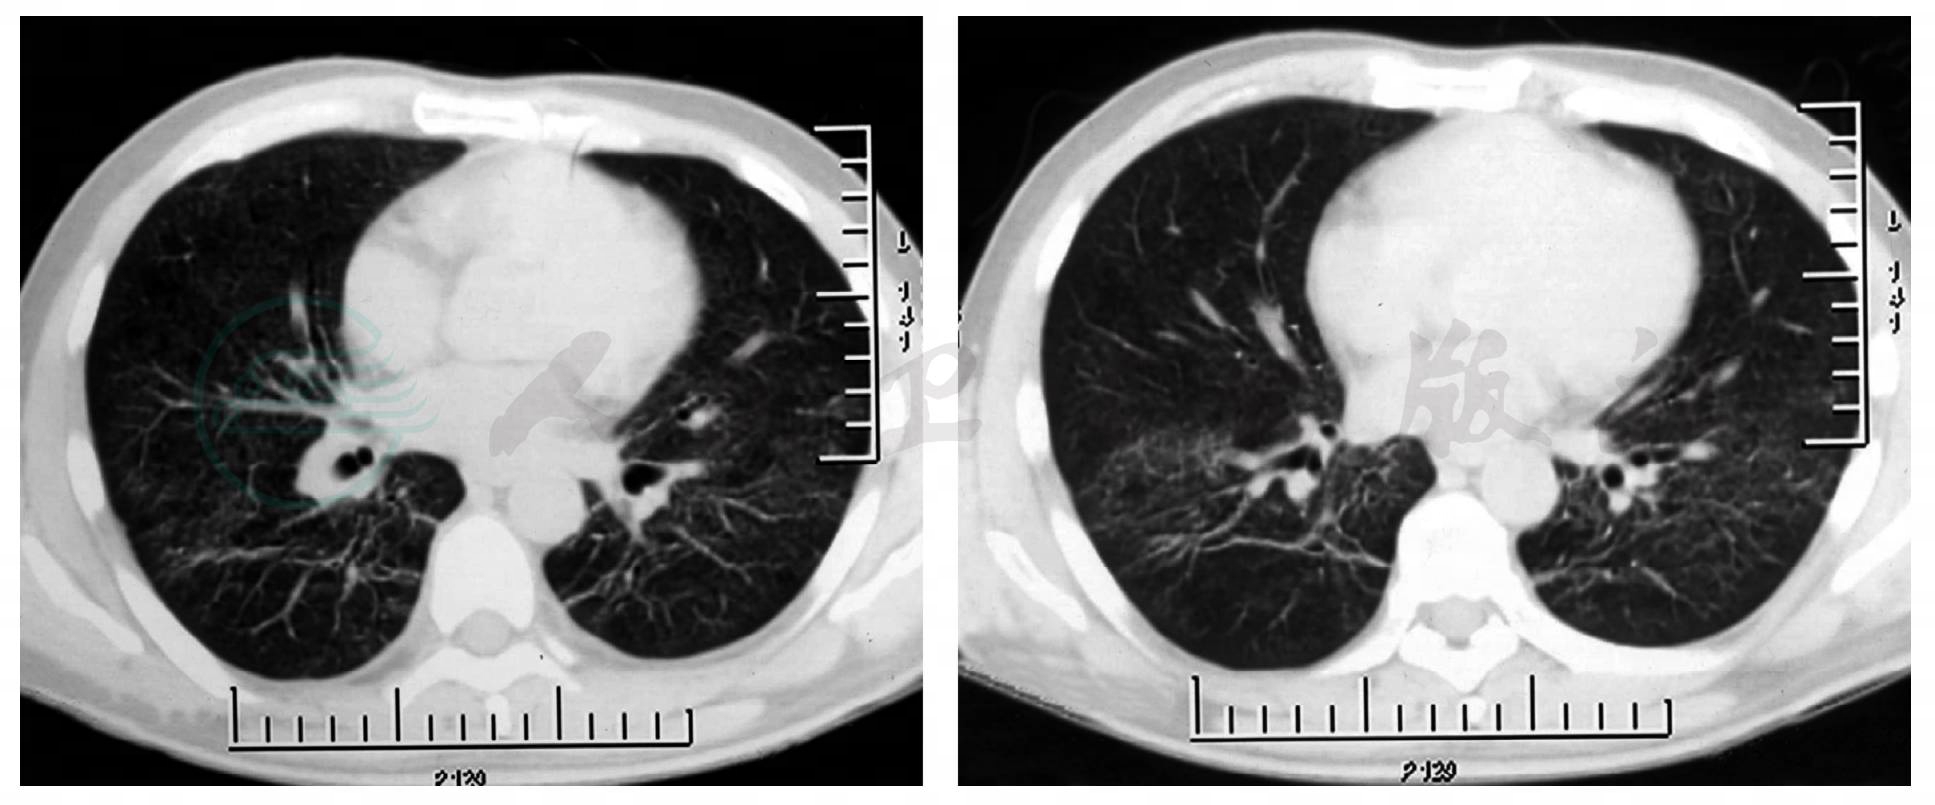

7.胸部影像学:胸部CT示双肺点状高密度影,磨玻璃样改变(图1)。

图 1 胸部影像学

重要的检查结果有两项:①静脉血淋巴细胞百分比增高,CRP、ESR增高;②胸部影像学示双肺多发浸润影;结合患者的病史和体格检查结果,进一步支持感染性疾病——社区获得性肺炎(community acquired pneumonia,CAP)的诊断,但目前病原学尚不明确。